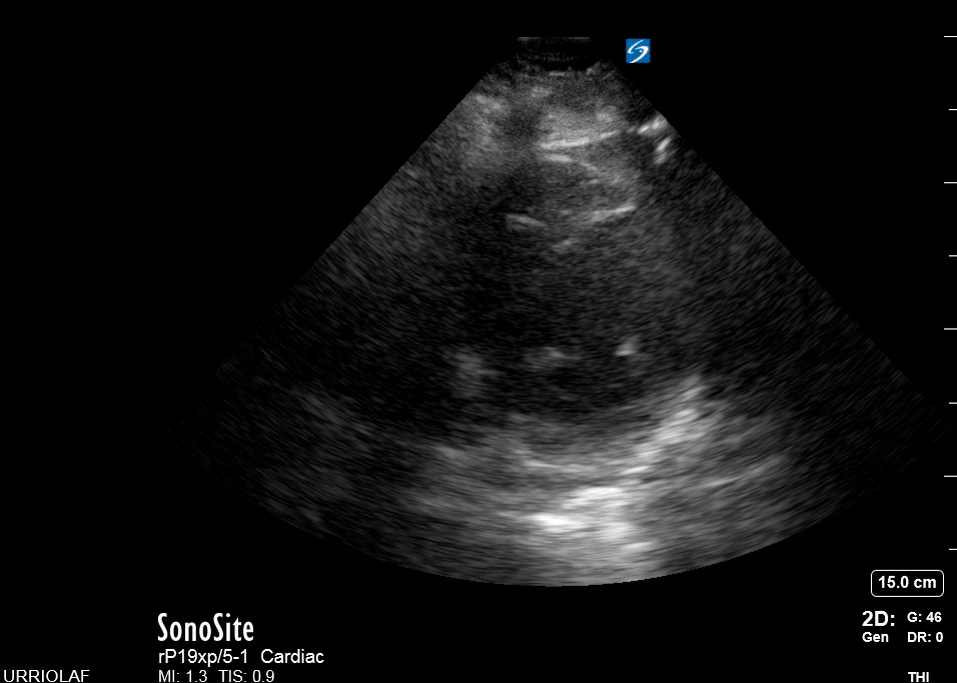

This view looks at the heart from the apex. When done properly, it achieves a horizontal cut of the heart that demonstrate all four chambers simultaneously. Consequently, its main utility is to assess the relationship between LV and RV. Beware, differentiating the chambers by ventricle size or thickness is not recommended, and it could lead to confusion in case of RV enlargement.

ORIENTATION & TECHNIQUE

Place the transducer at the apex beat and angle it towards the right scapula. The correct image results from sliding the probe until the interventricular septum is in the middle of the screen, vertically dividing both sides of the heart. If using a cardiac preset, the probe’s marker points towards the patient’s left arm. Simpler, in this view, the probe notch should meet the marking on the screen, which is fundamental to avoid confusion.